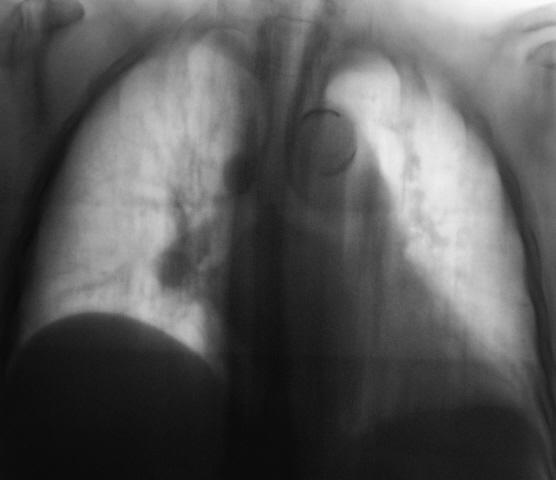

Картина ампутации левого нижнедолевого бронха, ателектаз нижней доли слева, диссеминация метастатической природы

Левый главный бронх оттеснен кверху, по всей видимости, за счет увеличения л/узлов бифуркационной группы?

Теперь о данном наблюдении. Оценка рентгенограмм к сожалению очень индивидуальный и субъективный процесс. Ход моих мыслей: пожилой пациент без жалоб, а на снимках выраженная диффузная патология в грудной клетке - сразу включается механизм перехода мышления на онкологические рельсы. Я много лет работал в детской торакальной хирургии, поэтому так насторожен и "кидаюсь" на малейшие смещения средостения - мне показалось, что есть смещение сердца влево. Конечно, лучше, чтобы снимок был чуть более жестким, и на нем не было бы абсолютно непрозрачных мест, но что имеем...

Внутри тени сердца, параллельно контуру левого желудочка внизу есть дополнительный контур, который я расценил как наружную границу уменьшенной левой нижней доли, отсюда и все мои последующие выводы. Именно эти места уже отмечены Вами желтыми стрелками - просто наши оценки одного и того же различаются. Насчет четкой видимости ампутации бронха - согласен, двоечтение возможно.

В литературе и на практике встречал 3 основных варианта картины ателектаза нижней доли слева. Для всех них в прямой проекции характерно легкое смешение сердца влево, повление интенсивной треугольной тени за сердцем слева медиально, второго контура за сердцем. Но в боковой проекции картина разнообразна (в какой плоскости преимущесвенно сложится доля - как веер) и сводится к трем основным вариантам:

В отличии от уважаемых коллег, я не увидел признаков ателектаза ни слева, ни справа, при этом согласен с наличием диффузных изменений, в сочетании с увеличением лимфоузлов в обоих корнях. Диф. ряд весьма широк.